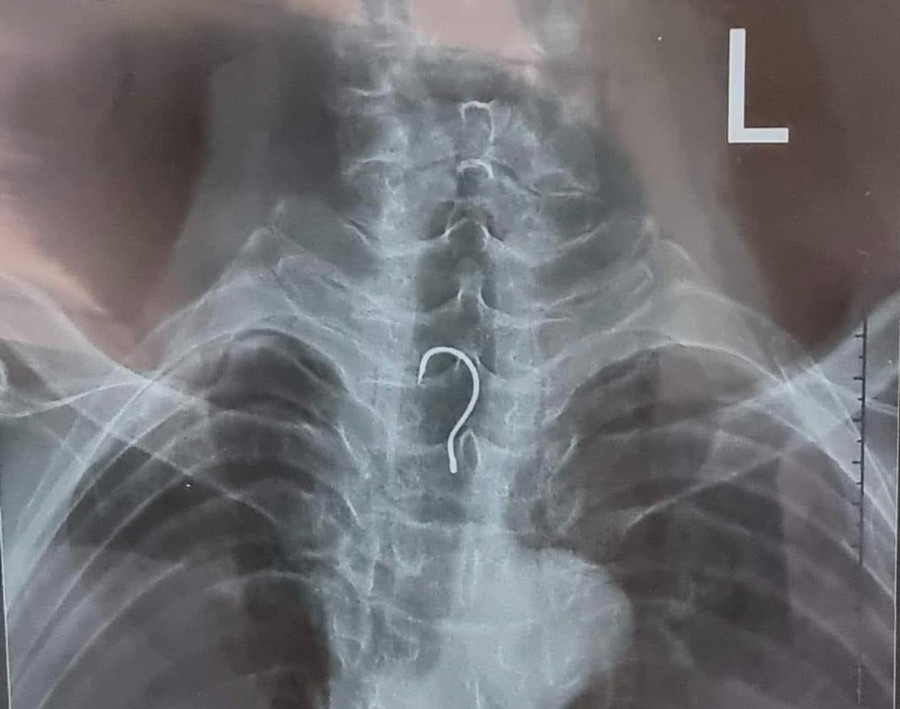

Kết quả, qua nội soi, các bác sĩ phát hiện dị vật nằm ở trong khu vực thực quản của bệnh nhân. Ngay sau đó, ê-kíp nội soi đã gắp ra ngoài dị vật là một chiếc lưỡi câu có chiều dài gần 4cm, vòng cung rộng gần 1,5cm.

| Hình ảnh chiếc lưỡi câu mắc kẹt trong thực quản bệnh nhân. |